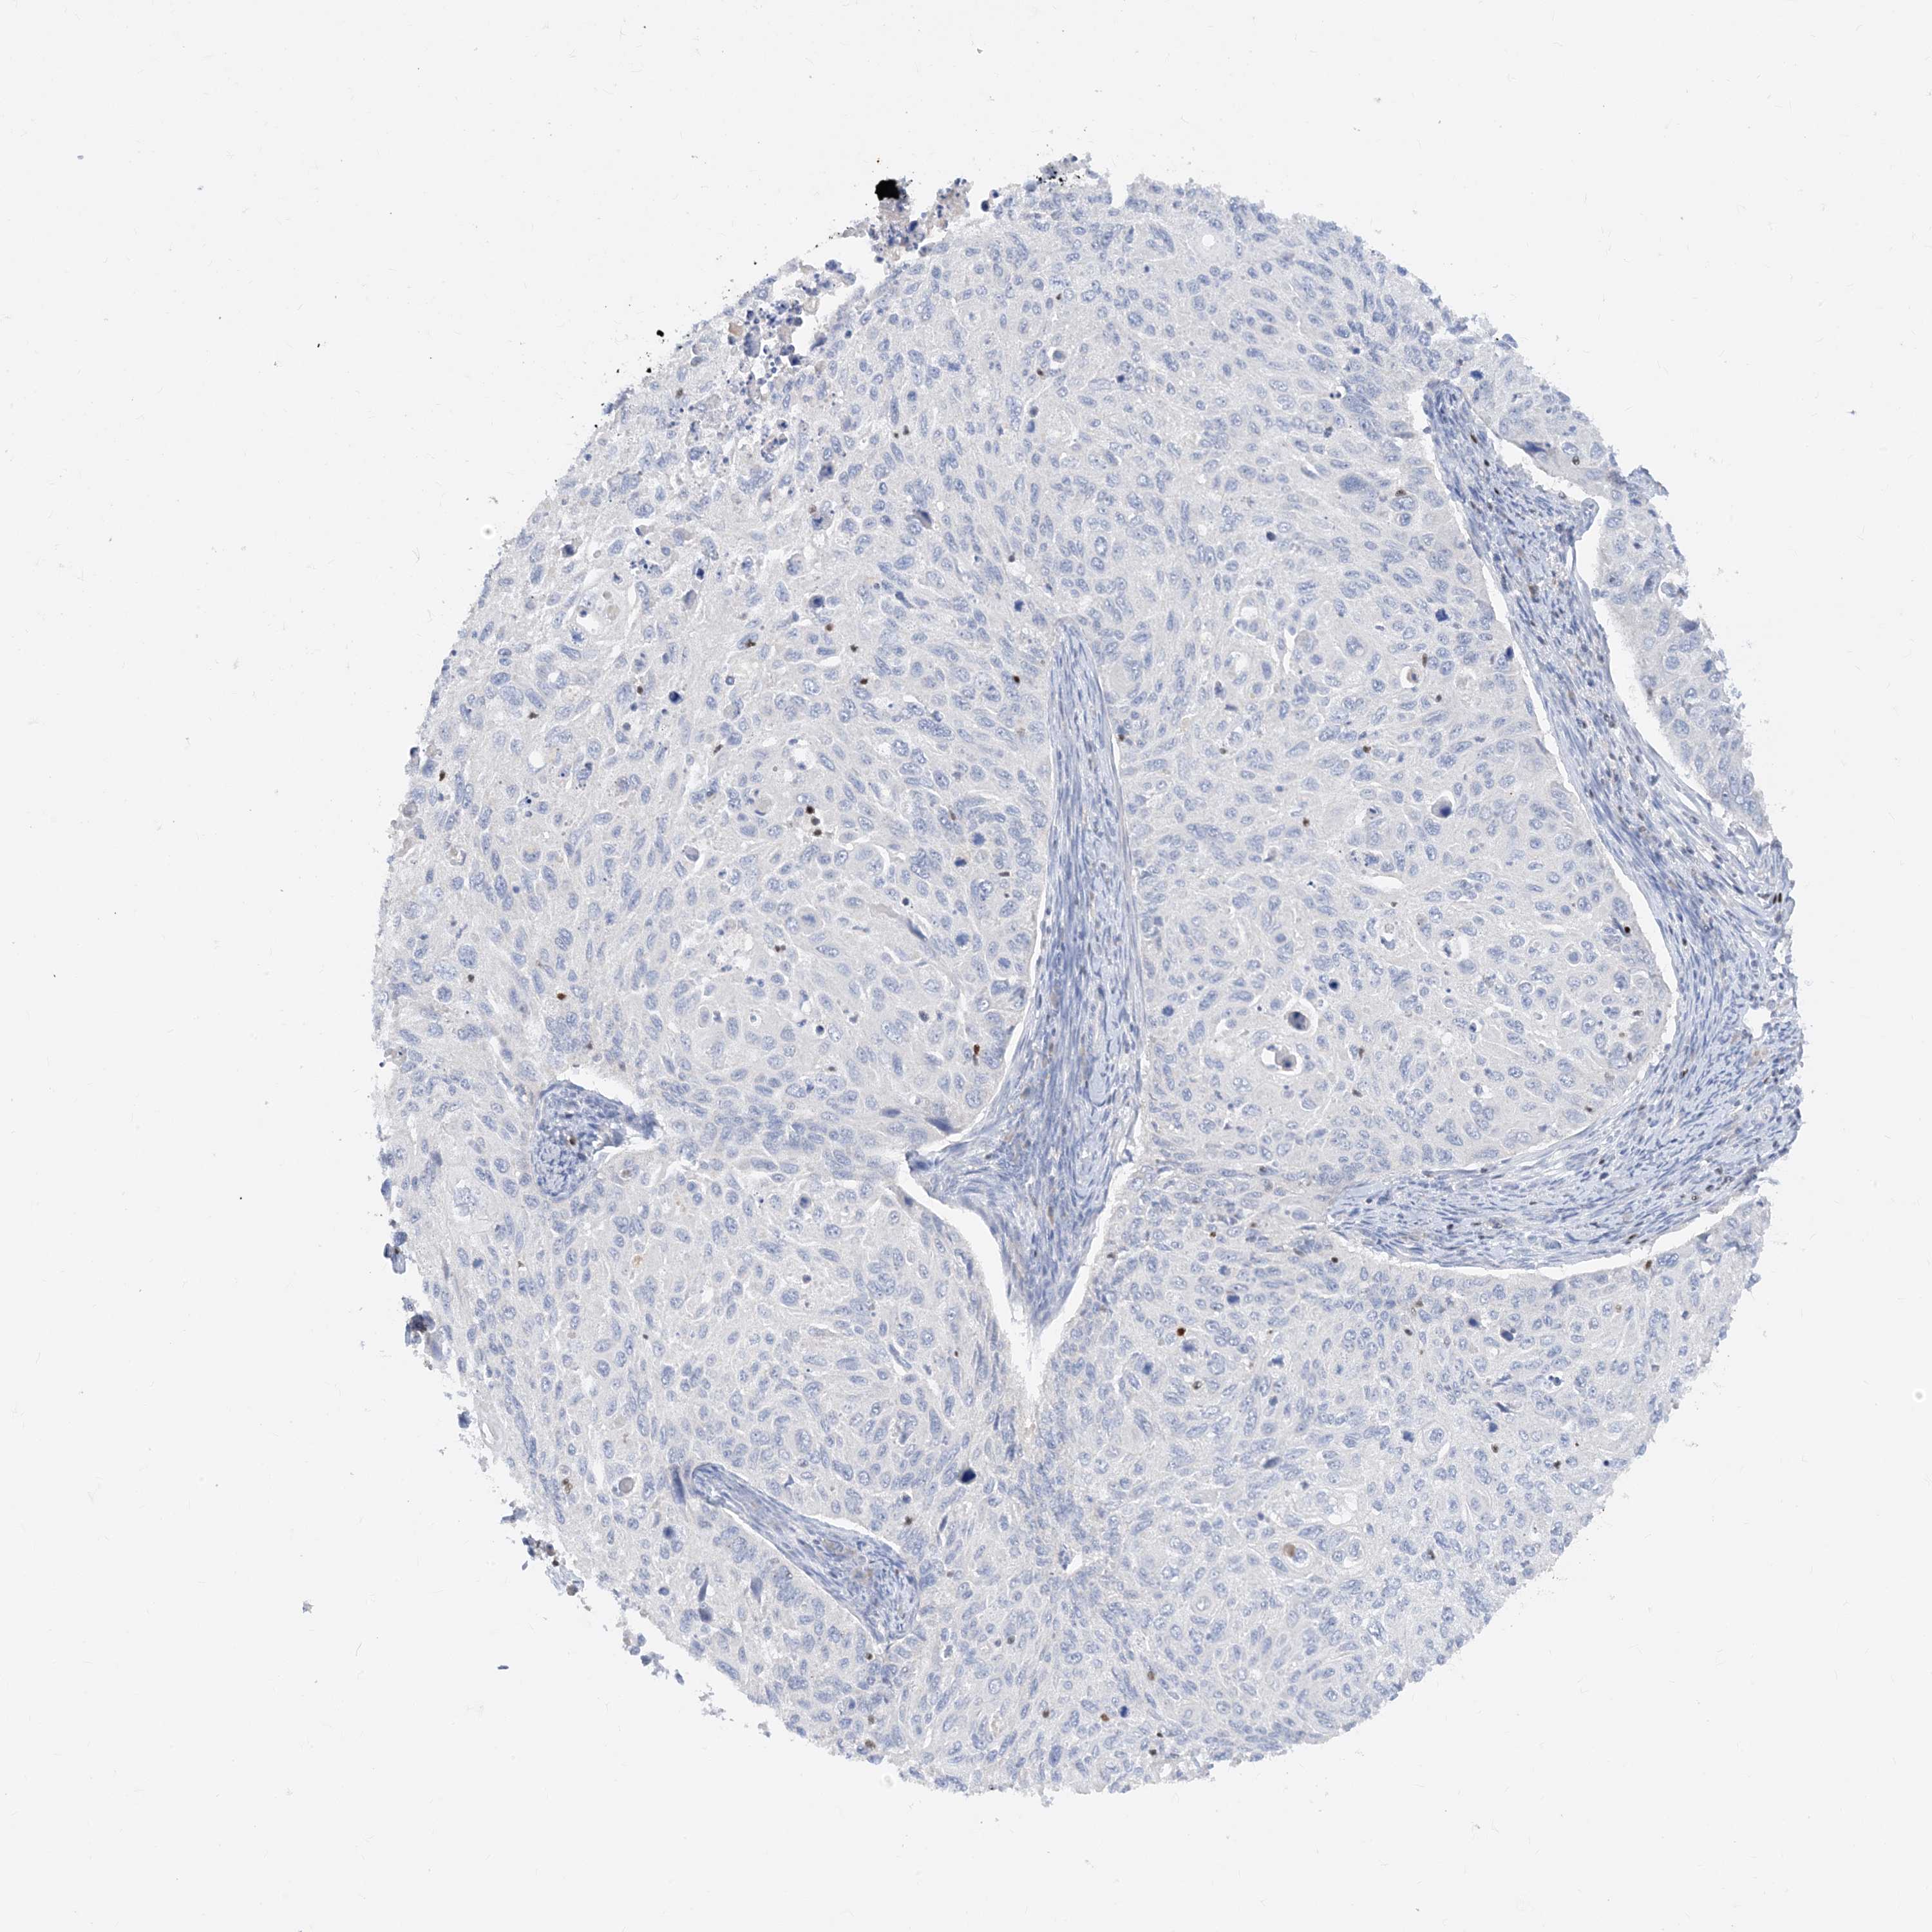

TBX21